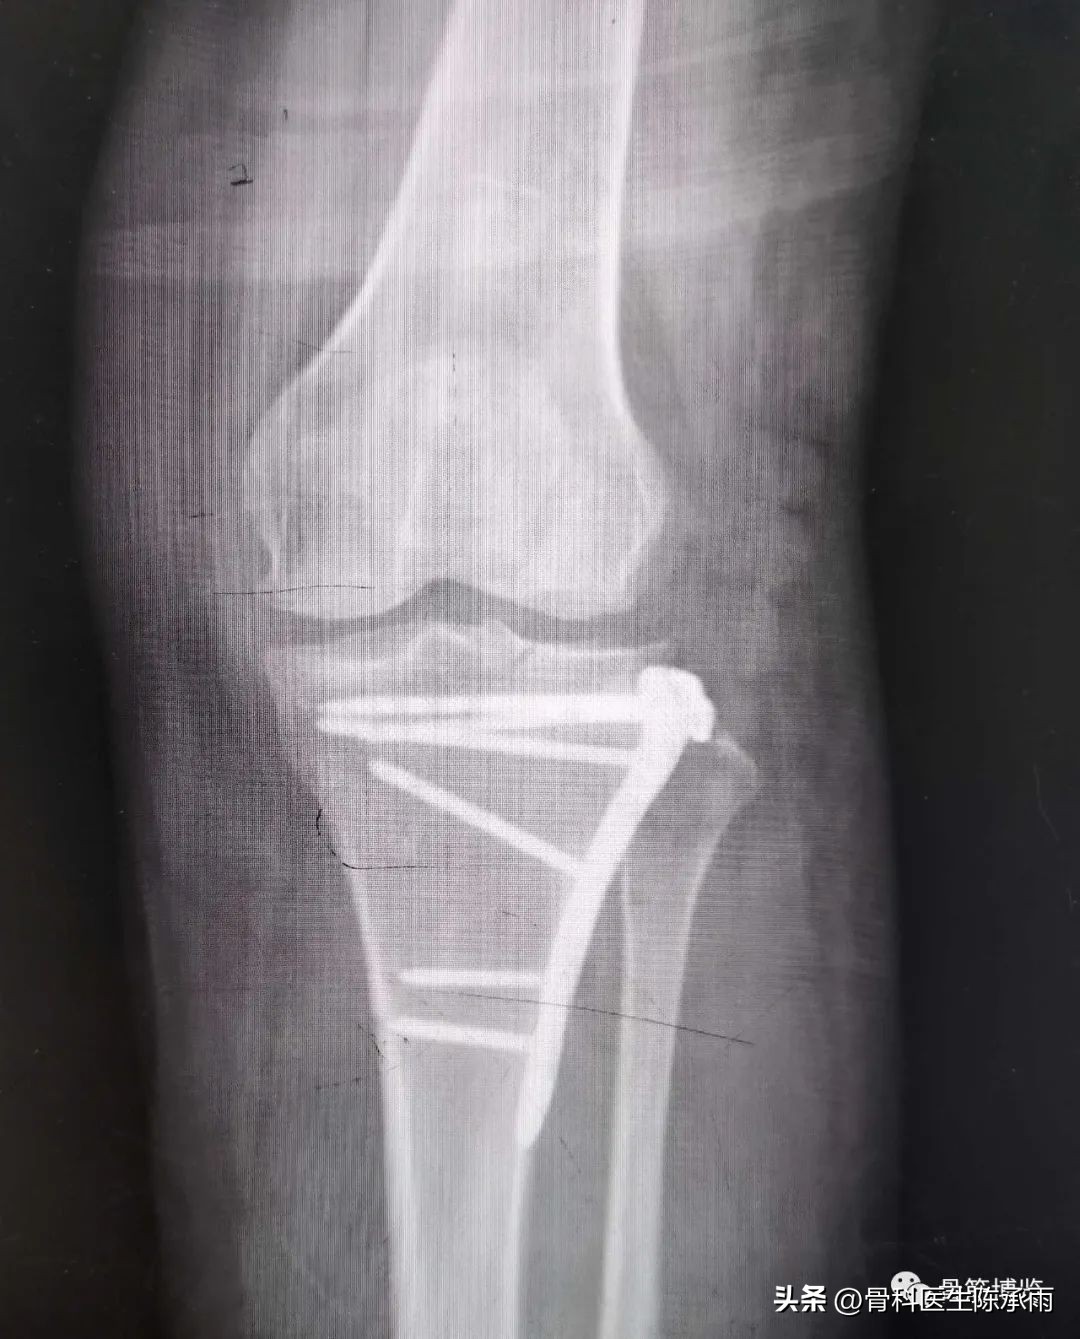

近段时间的胫骨平台骨折,没来得及详细整理

胫骨平台骨折的分型比较多,我们临床上常用的就是Schatzker分型和AO骨折的分型,还有骨折脱位的Hohi-Moore分型,这是我们常用的三个分型。

对AO 分型来讲,现在这是AO推出来更详细的,再分为ABC。随着分型的增加,从A到C骨折的损伤程度是越来越重,治疗也越来越困难,从1到2 ,123也是这个规律,骨折的分型就是给我们表明了骨折的一个损伤的程度,治疗办法和损伤的特点。我们对于骨折脱位的分型,常用Hohi-Moore分型,这个是弥补了,Schatzker和AO分型的一些缺陷。